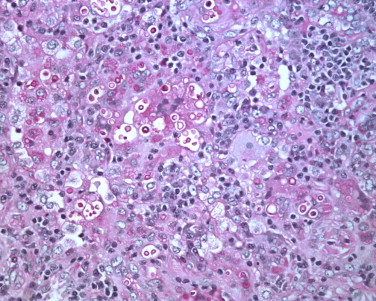

La tinción con hematoxilina y eosina (H&E) es una técnica de tinción histológica ampliamente utilizada en la microscopía para visualizar las estructuras celulares y tejidos en cortes histológicos. A…